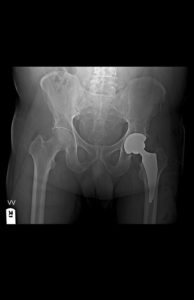

The Direct Anterior Approach is a modern, muscle-sparing technique that accesses the hip joint from the front of the body. Unlike traditional hip replacements that cut through major muscles, Direct Anterior Approach Hip Replacement Surgery allows surgeons to work between muscles, reducing trauma and accelerating recovery. Therefore, patients often experience a faster and more comfortable healing process.

For patients worried about a long and painful recovery, the anterior approach is a breakthrough. In addition to minimizing surgical trauma, it offers::

- Minimal muscle damage

- Less post-operative pain

- Quicker return to daily life

- Smaller scar and lower dislocation risk

- Shorter hospital stay – sometimes even same-day discharge